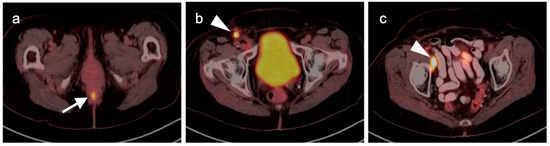

10. Anal Carcinoma